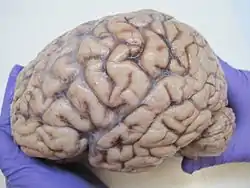

The human brain, obtained after an autopsy | |